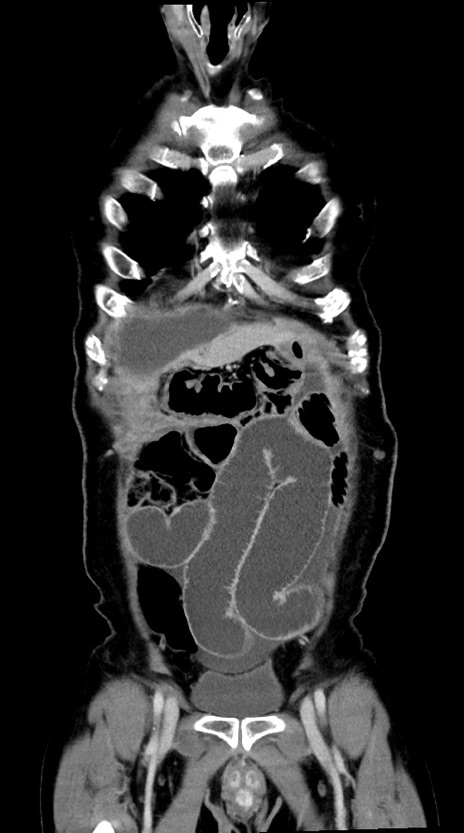

症例28(冠状断像)

【症例】60歳代男性

【主訴】嘔吐

【現病歴】胃癌にて胃全摘後。食思不振が悪化し、夜中に嘔吐することがある。

【既往歴】胃癌、胃全摘、脾摘、胆摘後

【データ】WBC 5900、CRP 10.56